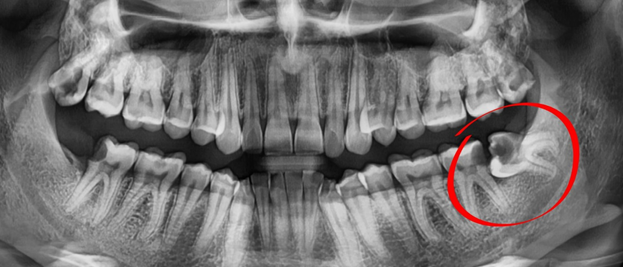

- Chụp X-quang hoặc CT Cone Beam 3D để kiểm tra vị trí răng khôn, mức độ xương hàm và khả năng ảnh hưởng đến răng khác.

- Chụp CT Cone Beam 3D xác định vị trí, hướng mọc, độ nghiêng, số chân răng và mối quan hệ với dây thần kinh, xoang hàm, răng số 7.

- Chụp X-quang CT Cone Beam 3D: Xác định chính xác vị trí, hướng mọc và cấu trúc xương quanh răng khôn.